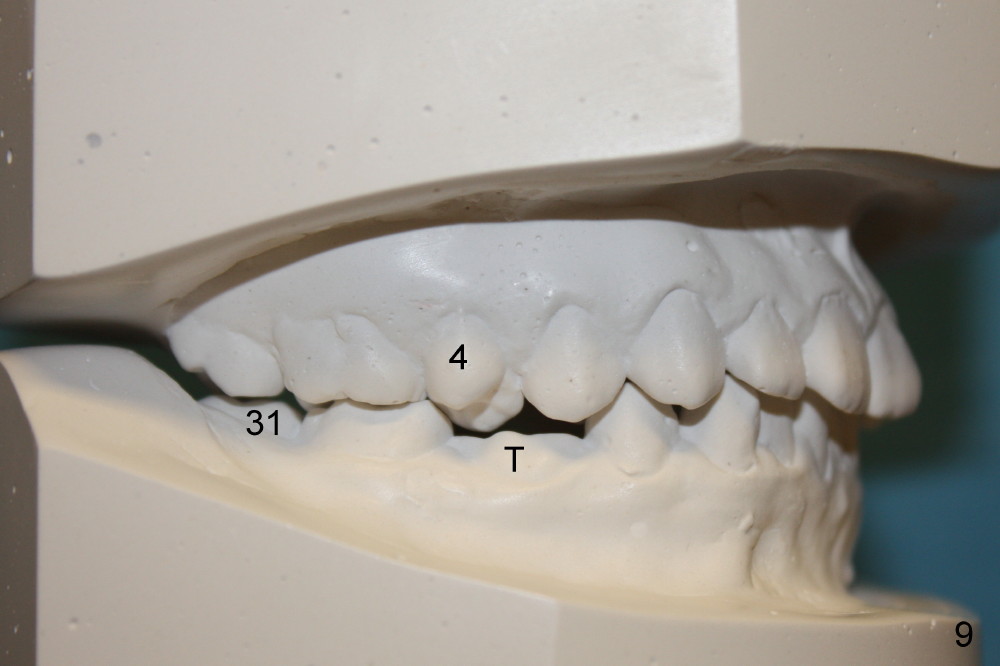

A 13-year-old Asian girl seeks orthodontic treatment for crowding. The lower 2nd bicuspids are congenitally missing (Fig.1,8), whereas the upper right one rotates 180° and the upper left is partially impacted (Fig. 1, 7). The lip muscles strain when the lips close (Fig.3). Orthodontic treatment started with extraction of four affected teeth (#4,13, K and T) 6 months ago. .018' niti wires are being used. Dental midlines do not coincide preop and intraop (Fig.4,4'). Pre-op front view shows that the upper dental midline coincides with the facial one (Fig.1'). There is Class I canine and molar relationship on the right (Fig.5,5',9,9'); open bite on the left (Fig.6,6',10,10').

Next steps: 1. Use elastics to close open bite on the left and to upright #31 (linguoversion, probably #18 to lesser degree) (Fig.8,8',9,9'); 2. Shift the lower midline to the left before closing 2nd bicuspid spaces. What is the best way to close spaces? Power chains for both arches or closed coil springs for upper and loop for lower (which is used for Tiffany Yue)? Since intraop profile is acceptable (Fig.2',3', as compared to Fig.2,3 (preop)), molars will be mesialized.

Update: The left open bite was closed less than one month by wearing elastics between upper and lower teeth (Fig. 6'''). The occlusal plane and midline improve (Fig.4''). Wires have gradually changed to .016x.016, .016x.022 and now .018x.025 with power chains. All the spaces are closed except the one in LR (Fig.7''-10''). What I cannot accomplish is to fix meisal (Fig.5'' (white line), 9'') and lingual (Fig.8'' arrows) inclination of LR molars, although elastic is instructed to be placed between UR7 buccal and LR7 lingual. The rectangular wires could be twisted to fix lingual inclination. Which should be done first: LR space or LR molar inclination? Click each figure for magnification.